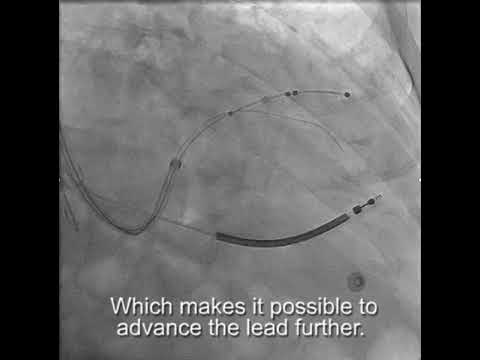

Video: With a sub-selector secure in the vein a soft stylet can be used to advance the LV lead deeper.